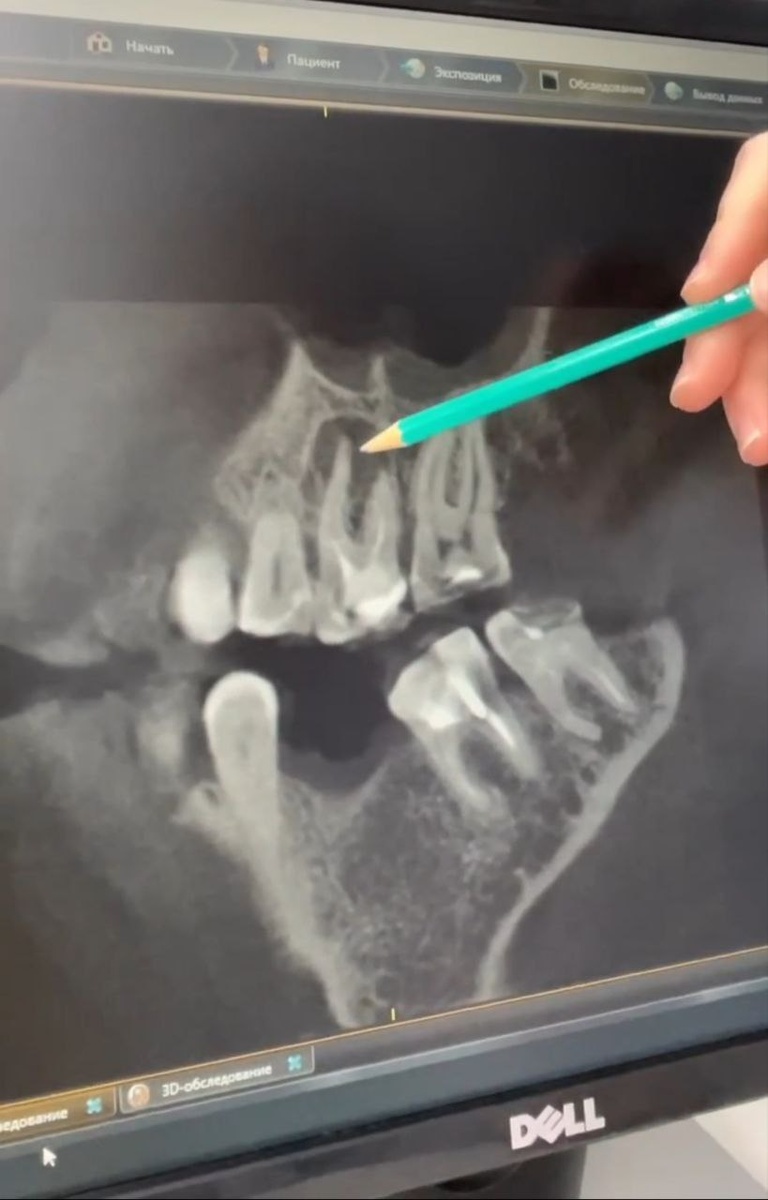

В клиниках ПРАЙМ пациент сначала проходит КЛКТ-диагностику, после которой врач принимает решение, какой метод лечения лучше выбрать.

Чаще всего это апикиальная хирургия (частичное удаление инфицированной верхушки корня зуба) или повторное эндодонтическое вмешательство, т.е. перелечивание каналов зуба с помощью микроскопа.